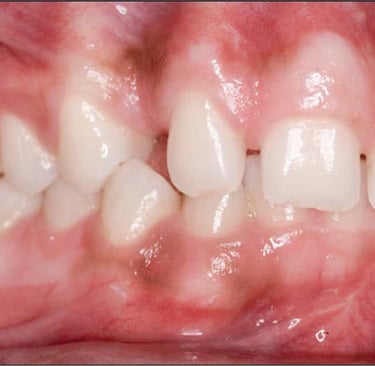

Impacted maxillary canines—where the upper canine teeth fail to erupt properly—are a challenging issue for orthodontists, affecting roughly 1-2% of the population. These teeth play a crucial role in your bite and aesthetics, but when they remain impacted, they can cause crowding, misalignment, and damage to adjacent teeth. While traditional braces have been the standard treatment, clear aligners are now gaining popularity as a more discreet and comfortable option. However, treating impacted canines with aligners comes with specific challenges that require careful management.

Impacted maxillary canines are difficult to treat because of their deep position in the jaw and the need for precise forces to move them into place. For treatment to succeed, the canine must be guided slowly along its eruption path while creating enough space for it in the dental arch. Traditionally, braces with their ability to exert stronger and more controlled forces have been preferred. However, advancements in aligner technology are making clear aligners a viable option, especially for patients who prioritize aesthetics.